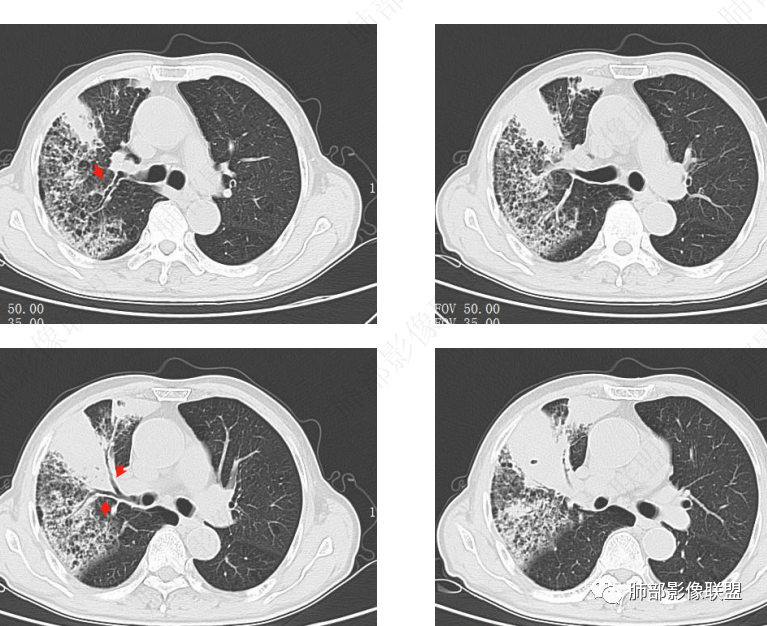

老年男性,乏力纳差,进食量明显下降,发热,后期少许黄脓痰,无咯血。无胸痛。未提口腔卫生情况,发热时间段不明确,肺气肿背景,气管内痰拴还是其他?觉得是外朝内进展病灶,右肺多叶段病灶,支气管通畅,支气管壁弥漫增厚,实变病灶内有坏死,坏死边界比较清晰,血管破坏不明显,周围散在磨玻璃,边界模糊,无树芽,实变内可疑小钙化,右侧胸水,肺门纵隔淋巴结无明显肿大。病史不太支持化脓菌感染,真菌里隐球强化不太支持,结核需要排除,厌氧菌感染带排,冠状位矢状位病灶觉得类圆形,临床肿瘤也是不能轻易排除的

发热,炎性指标高。右肺上叶实变影,凝固型坏死,裂隙状空洞,有钙化,有间质结节,考虑感染性病变,TB可能,鉴别肺炎性肺癌。

病灶1、2、3,怎么用鳞癌、腺癌解释?

这能用缺血性坏死解释吗?

肉芽肿性炎,支气管肺炎,坏死性炎,

上肺优势;3是血管侵袭

奴卡>放线菌

2呈现奴卡之角

这个病灶,鳞癌肯定可以排除了

腺癌、放线菌也不符合,奴卡解释可以

南边:老年男性,20天病史

自服草药就不好说,疗效不佳,38.7度,这些提示感染

肿瘤标志物不高,主病灶在前段

前段大一些的支气管通畅

两个病灶独立,又有关联性,内侧病灶近端的支气管包绕在外侧病灶之中,但是走形自然

无堵塞迹象,支气管壁弥漫增厚

腔通畅

内部大片坏死区,其中还有不规则空洞

坏死腔内壁清,有强化环

肺动脉在实变区走形自然,坏死腔周围受压推移,走形自然,坏死区内破坏

周围GGO,不能考虑癌性淋巴管炎

1、中央型肺癌:腔内为主——堵塞,不符合,支气管还是通畅的;腔外为主,不符合,会在肺门区周围团块,而不是远端

2、外朝内蔓延的恶性肿瘤:肺炎型肺癌——坏死腔内壁光滑,内部是坏死中空洞,而非假大空,放待排。癌肉瘤?不是一个类圆形团块。

3、炎性病变:觉得蛮符合的

支气管壁弥漫增厚,周围GGO,粘液腺癌啊GGO是靠近病灶区密度高,外围低,这一例不是很符合

这类坏死区内空洞,提示坏死液比较粘稠

不是液化坏死,液化坏死,这么大,有气体进来按理会形成液气平面

凝固性坏死

结核,大病灶可以符合,就是周围大片GGO,而无树芽征,不踏实啊

上叶前段病变,中叶外侧段受侵。依据南大思路,感染病变更容易跨叶?是不是更支持感染

炎性多见,而且要警惕放线菌

炎性标志物升高,有悬浮气泡,是耍首先考虑放线菌